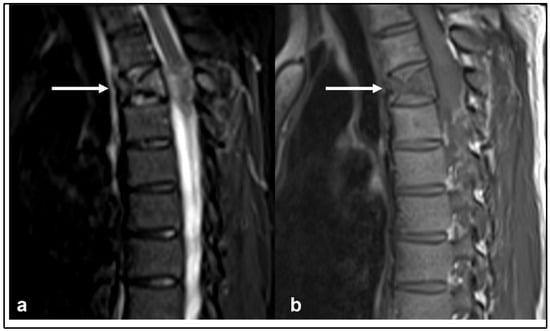

| Chordoma | Low attenuation lytic lesion. | Loculated high T2 signal mass, usually with extra-osseous soft tissue component. High T1 signal due to haemorrhagic and calcified components. |